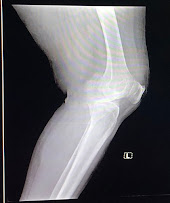

65 year old female with ??osteoarthritis

X-rays

Provisional diagnosis: osteoarthritis with hypertension and type 2 diabetes mellitus